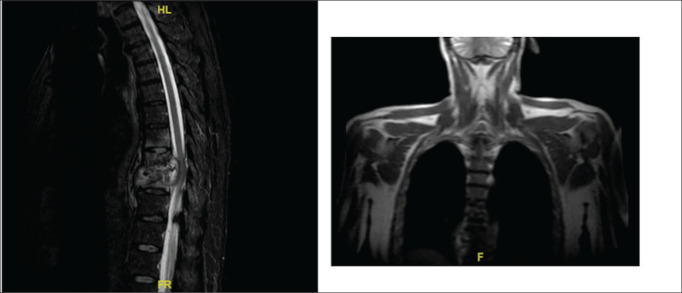

Results: In our analysis of 13 cases of Pott's disease, we observed a significant male predominance (69.23%) and diverse symptoms, with back pain (69.2%) being most prevalent among our patients. Lumbar involvement was the most frequently observed site (38.4%), and diagnoses were made through microbiology (69.2%) or clinical/radiological means (30.8%). Acid-fast bacilli (AFB) culture testing exhibited a positivity rate of 61.5%, while TB-PCR showed positive results in 57.1%. Imaging studies revealed vertebral lesions (90.9% CT, 81.8% MRI), abscesses (54.5% CT, 81.8% MRI), and spondylodiscitis (18.2% CT, 54.5% MRI). Treatment, administered in 92.3% of cases, involved the use of Isoniazid, Rifampicin, and Ethambutol. Surgical interventions, though less frequent, encompassed various procedures. Outcomes demonstrated a notable high cure rate of 84.9%, with a 15.4% incidence of cases experiencing loss of follow-up.